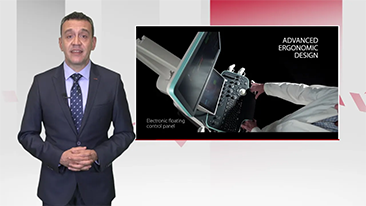

Solusi Pencitraan Umum Resona dari Mindray membantu para dokter mewujudkan diagnosis dan hasil pengobatan yang lebih akurat dan efisien melalui pemerik aplikasi subdivisi yang komprehensif dan alat bantu aplikasi klinis yang efisien.